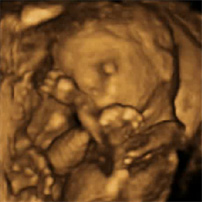

Desarrollo feto semana 17: El bebé se siente a sí mismo

El desarrollo del feto de 17 semanas es vertiginoso. En las próximas tres semanas el feto va a crecer tanto que duplicará su peso y altura, aunque aún se le ve muy flaco. En torno a la semana 17 de embarazo el cerebro desarrolla las vías neuronales que capacitarán al bebé para empezar a sentir las demás partes de su cuerpo, lo que se conoce como propiocepción.

? Aunque la propiocepción no madura por completo hasta después del parto, ahora aparecen los primeros indicios: por ejemplo el bebé empieza a juntar las manos, y si bien en un primer momento en cuanto se aproximan se separan, finalmente consigue unir sus dedos. Quizás los ha reconocido como propios.

? Físicamente el bebé se va poniendo guapo: ya tiene algo de pelillo en la cabeza, así como cejas y pestañas. Poco a poco su cuerpo se irá cubriendo de un pelillo muy fino llamado lanugo, que semanas antes del parto desaparece. Por eso algunos bebés que nacen prematuros aún lo conservan este vello oscuro, largo y fino en las orejas, sienes, mejillas, espalda y hombros.

? En los dedos de manos y pies tiene uñas.Una fina lámina cubre casi por completo el lecho ungueal, es decir la parte que hay debajo de las uñas y por donde crecen. Pero hasta el sexto mes de embarazo no estarán formadas por completo.

? Aún está muy flacucho porque todavía no ha generado grasa subcutánea. Además no para de moverse.